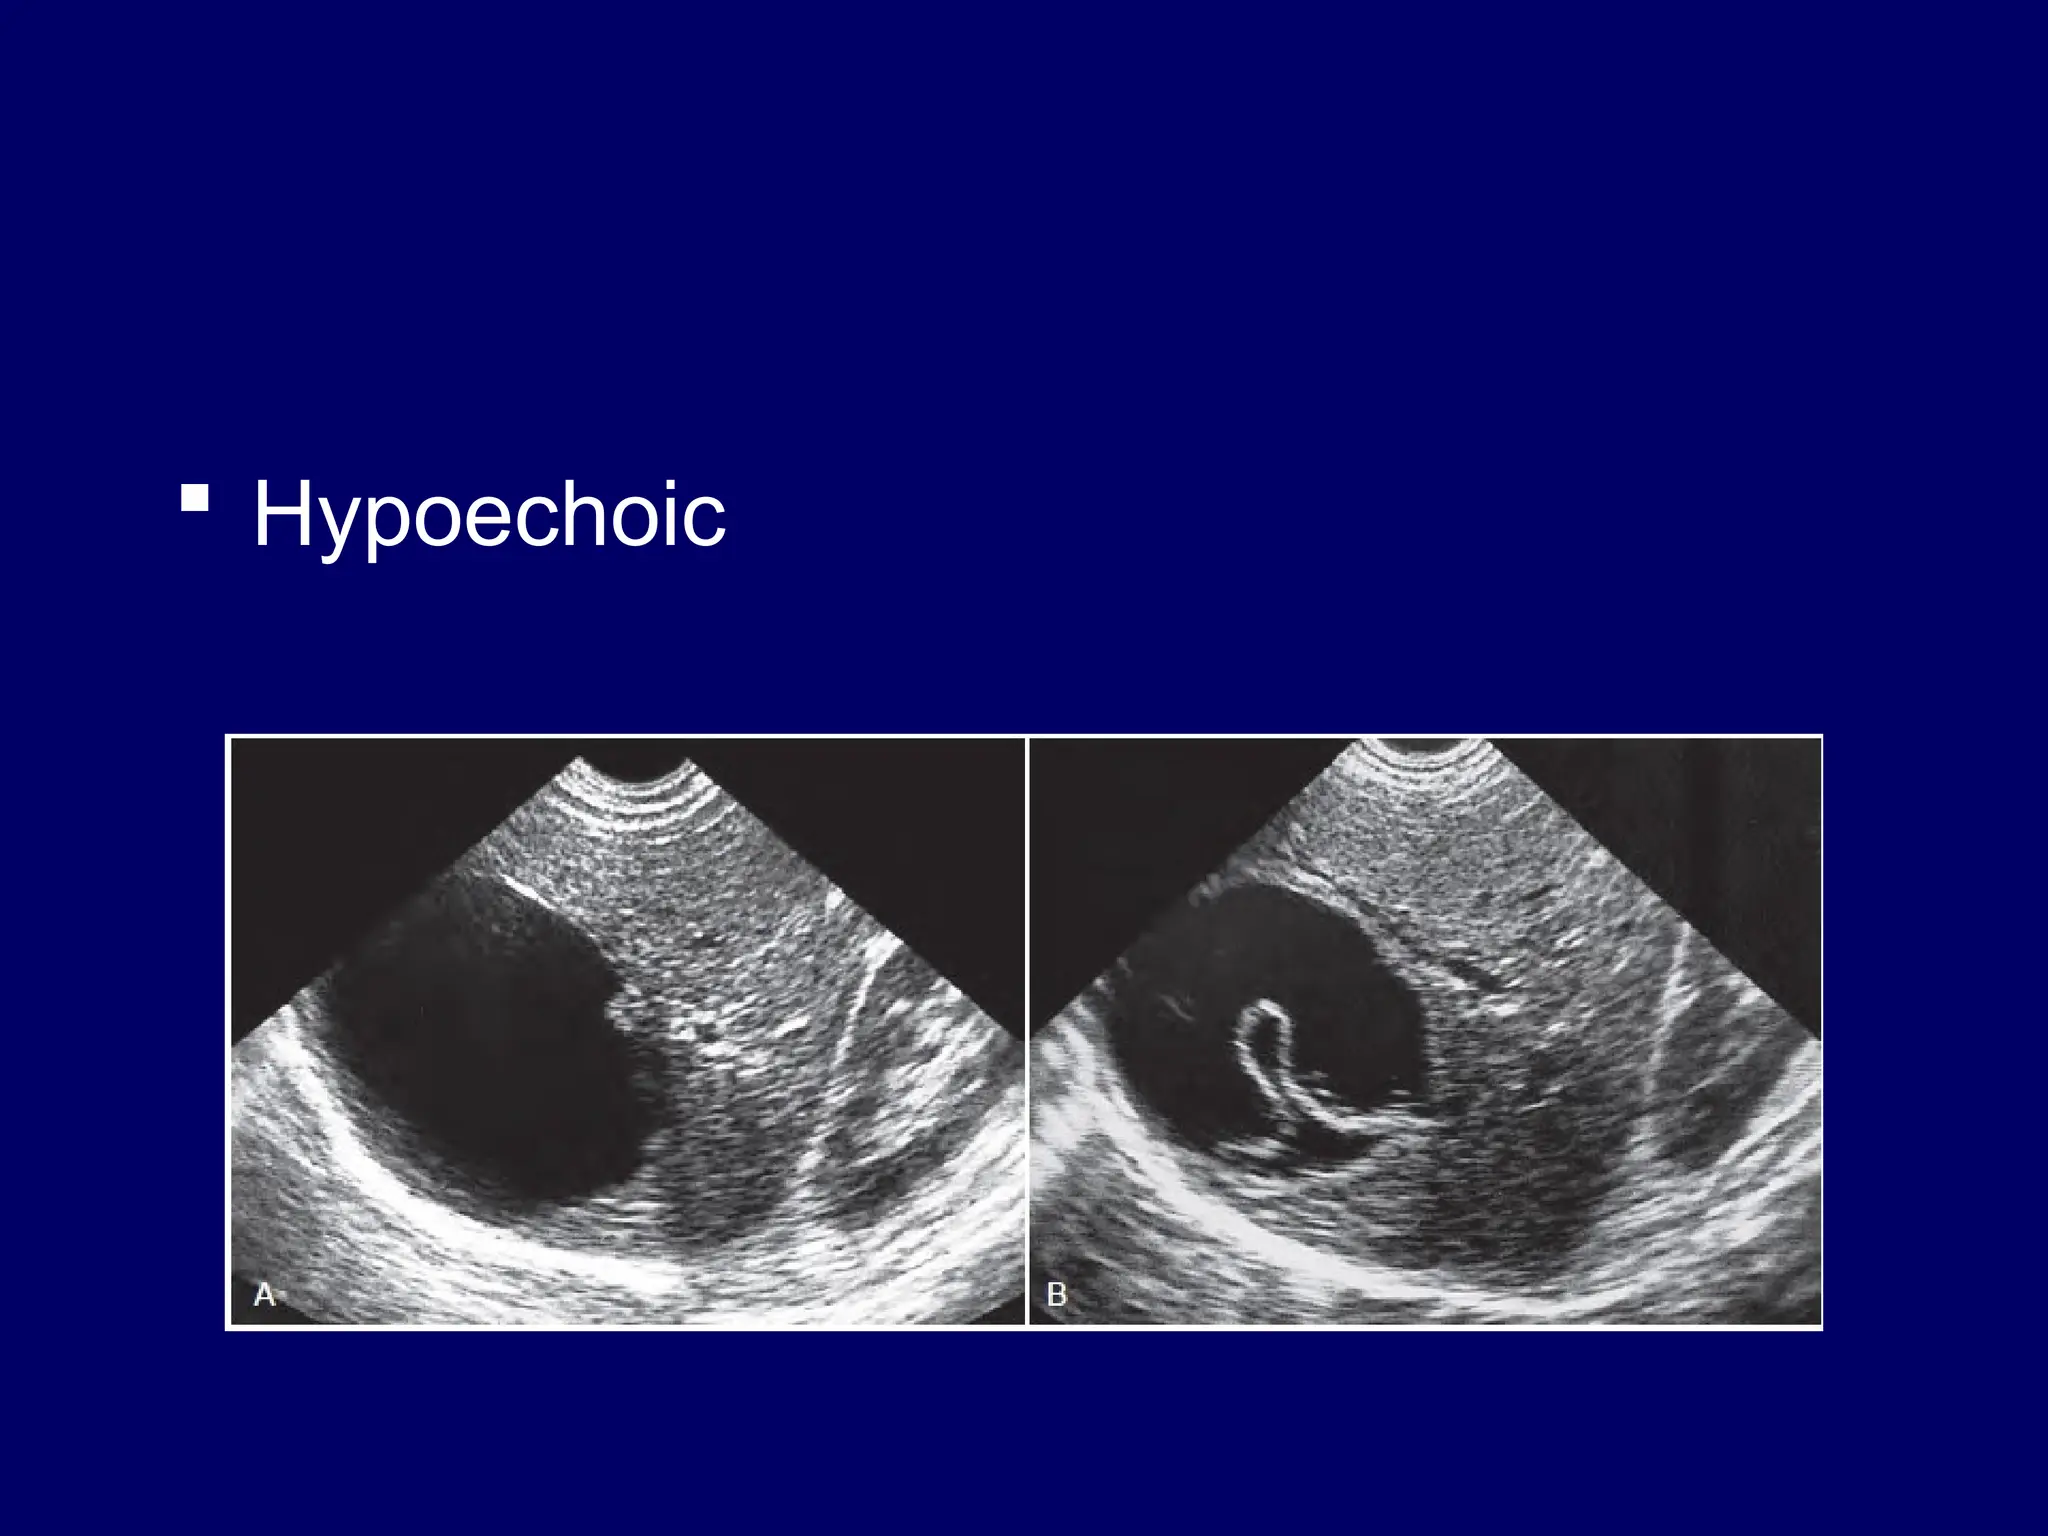

 Hypoechoic

Interpretation  Shadowing andthrough transmission – Acoustic shadowing – Acoustic enhancement – Edge shadowing  Echogenicity – Anaechoic…….black – Hypoechoic …..falls in btn black n white – Hyperechoic--white